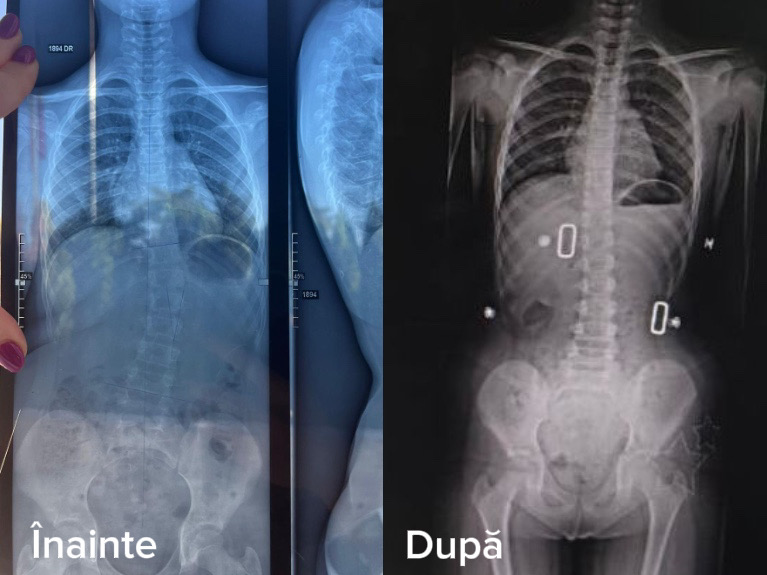

Sanconfind, cel mai mare spital privat din județul Prahova, vine cu o poveste medicală impresionantă: o fetiță de doar 9 ani a reușit să scape de scolioză după un program de recuperare urmat timp de șase luni în cadrul bazei de tratament a spitalului. Rezultatele sunt vizibile atât în radiografii, cât și în viața de zi cu zi a copilului: coloana este vizibil mai dreaptă, iar zâmbetele sunt mai largi, pentru că scolioza a devenit acum doar o amintire.

Radiografiile realizate în luna februarie 2026, arată o îmbunătățire evidentă a poziției coloanei vertebrale, confirmând eficiența programului de recuperare. Medicii spun că evoluția este foarte bună, iar fetița poate avea în prezent o viață perfect normală, fără limitări.